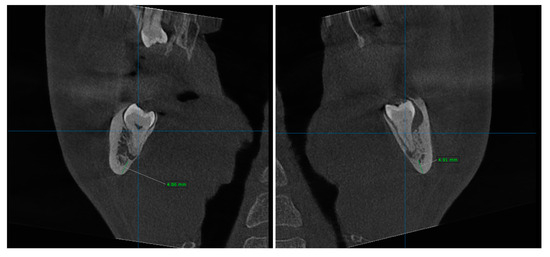

2.2. Pre-Surgical Cone Beam Computed Tomography (CBCT)

2.3. Design and Manufacturing of Customized Titanium Plates